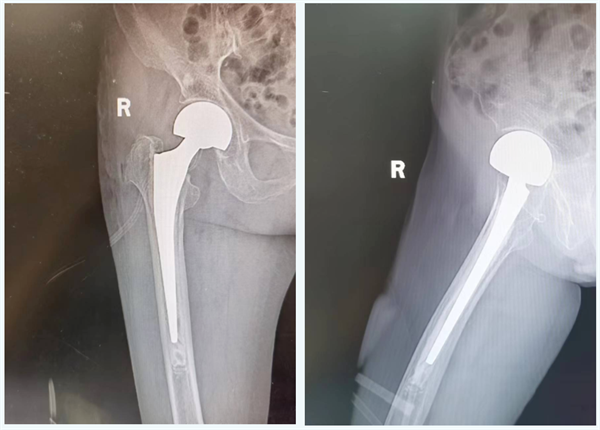

经我院骨伤科及麻醉科、心内科、呼吸科多科协作会诊,全面评估老人身体情况后与家属详细沟通,决定老人实施人工股骨头置换(骨水泥型)。在骨伤科医生丰富的经验和熟练的操作下,手术历时半小时顺利完成。

术后老人生命体征平稳,术后第二天便能下地站立、行走,在医师指导下进行功能锻炼,恢复良好,现已顺利出院。

术后影像: